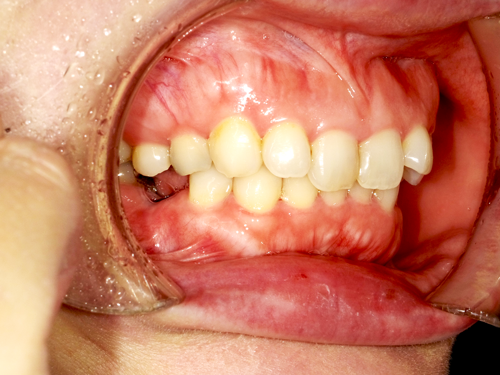

インプラントは、審美性の高い素材を使用でき、自然な仕上がりを実現可能です。ほり歯科・矯正歯科中央林間では、精密性の高い治療により、より美しい仕上がりを目指しています。